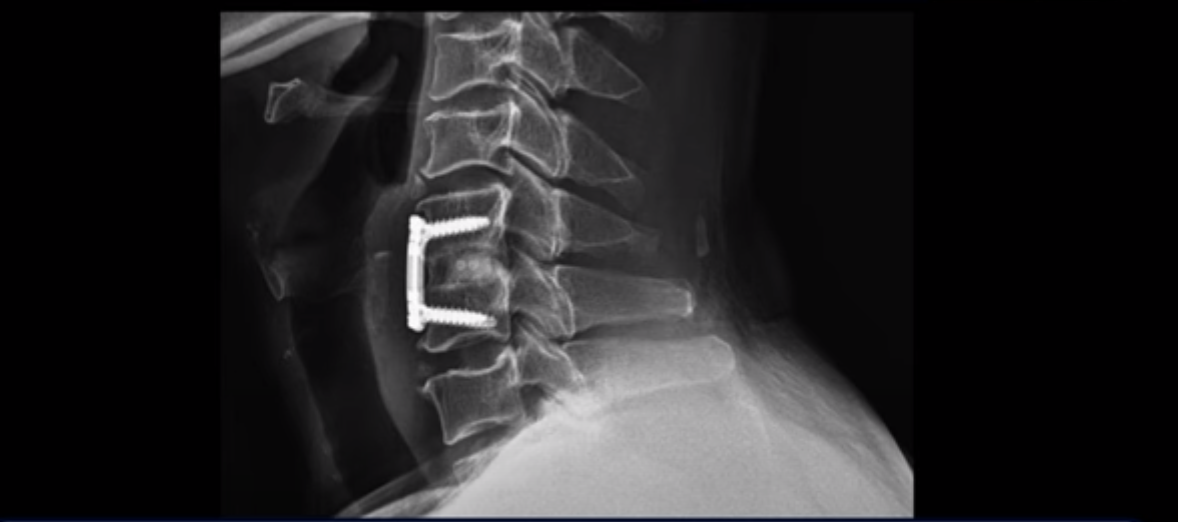

이분은 심한 목디스크로 인한 경추척수증 수술을 한 대학병원에서 22년 7월경 받으셨습니다.

수술은 잘 돼서 신경 눌림은 잘 풀렸다고 했지만 양쪽 다리 힘이 빠지고 비틀거리고 10m도 걷지 못하는 증상은 좋아진 게 거의 없습니다. 수술 후에도 양쪽 다리 감각이상, 특히 시린 증상과 화끈거림 그리고 통증도 심했고 감각기능도 많이 떨어진 상태 그대로였습니다. 수술 후 3년간 호전되지 않는 이런 증상들 때문에 양방치료, 한방치료 등 많은 치료를 여러 병원에서 받아봤지만 본인 표현으로는 조금도 좋아지지 않았다고 합니다.